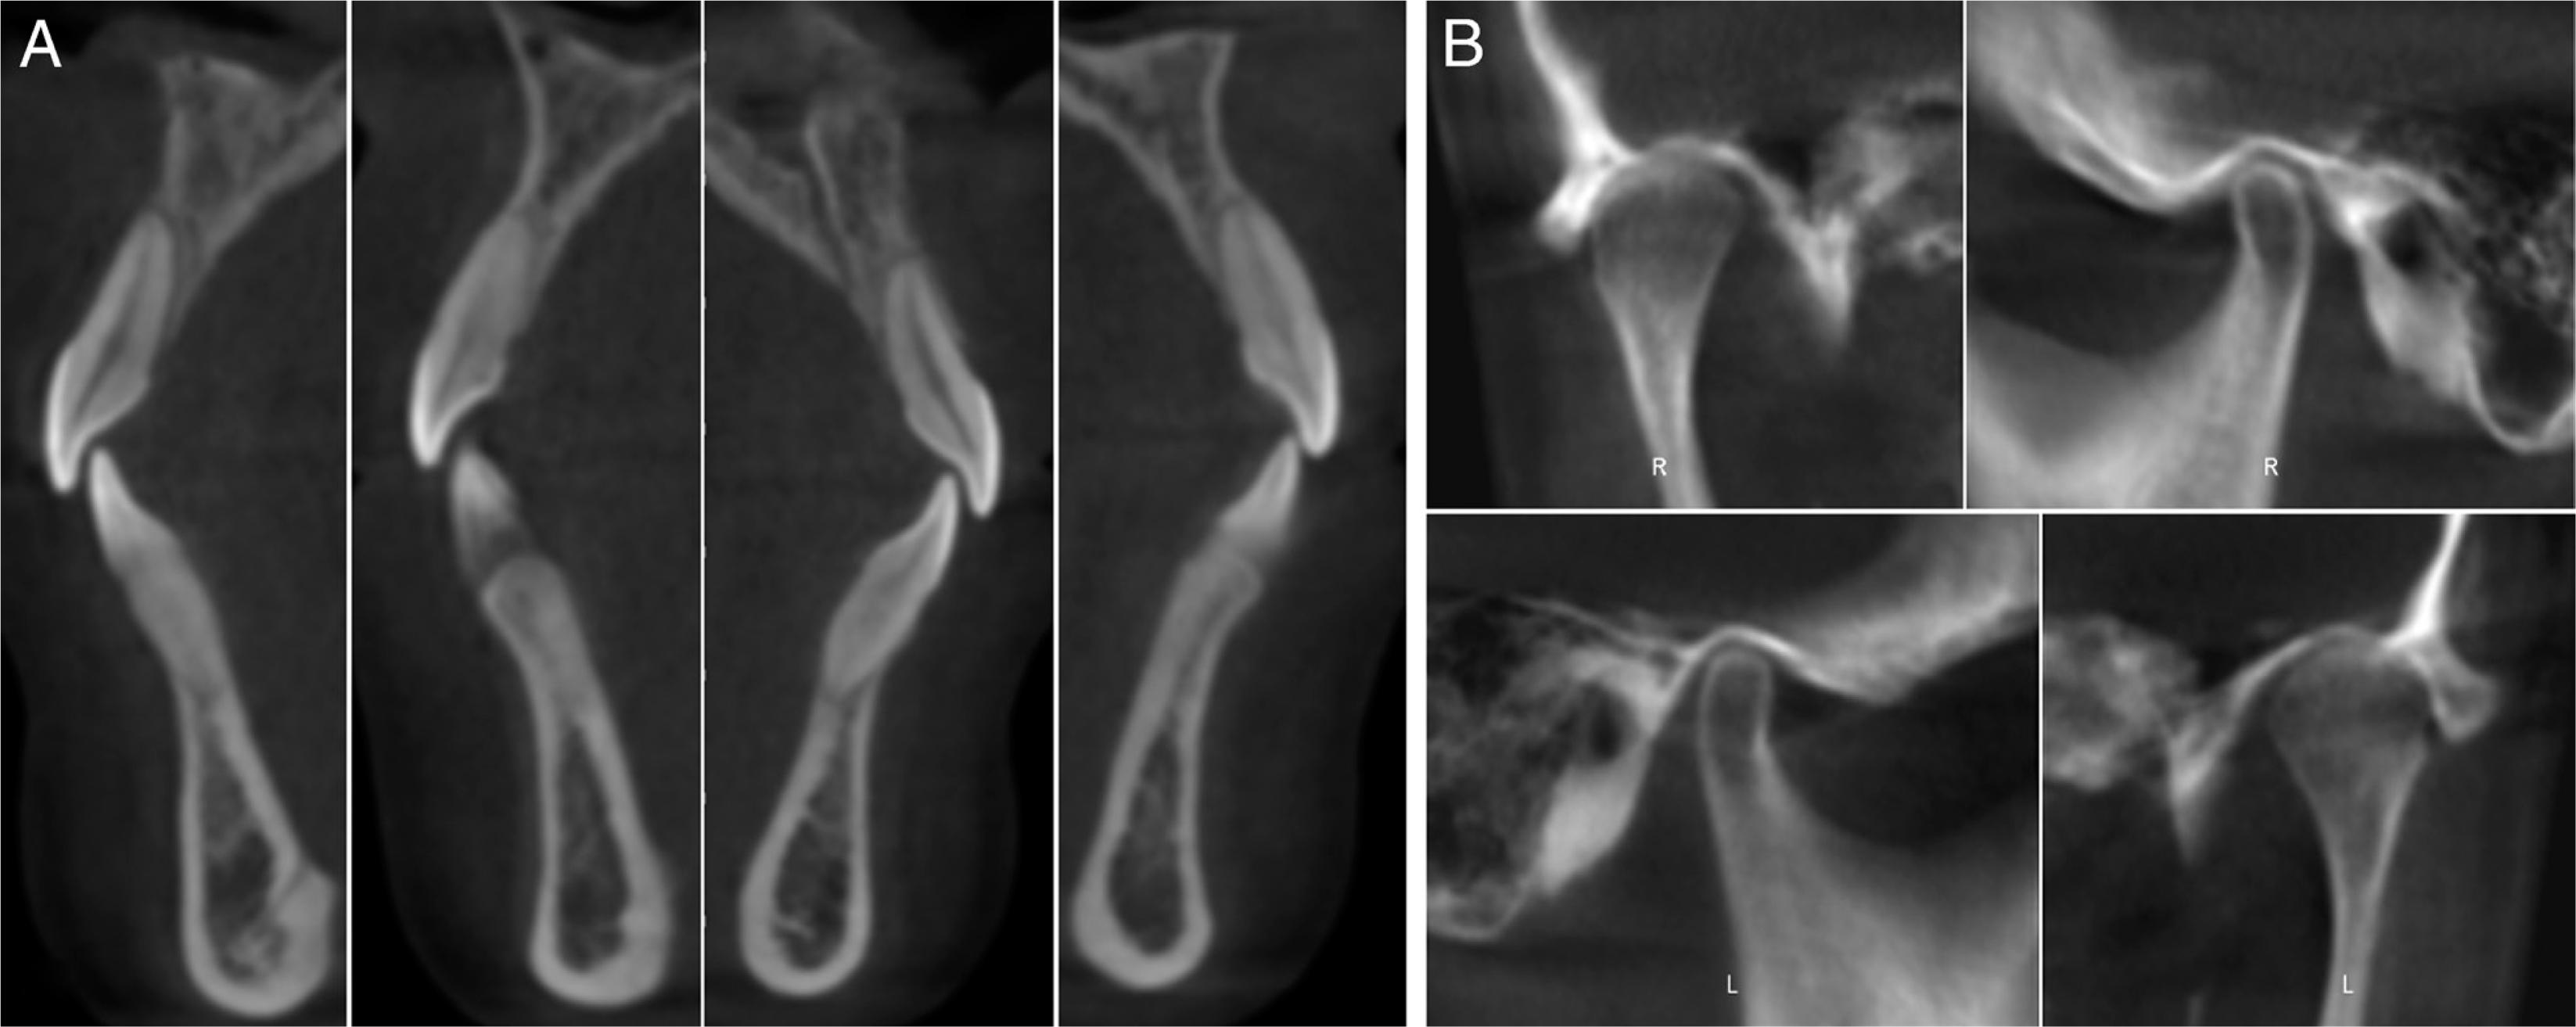

A 24-year-old female patient presented with a history of tongue thrust and mouth breathing but without a history of maxillofacial trauma or a non-nutritive sucking habit. The diagnostic records revealed that, based on the E line, the patient had a convex profile with a long face, a decreased nasolabial angle, a protrusive lower lip, and a shallow mentolabial sulcus. Further, the patient had incompetent and protruded lips at rest and in contact but with mentalis strain upon forcible closure. There was also a low smile line, and the smile arc was not consonant with the curvature of the lower lip (Figure 1). An intraoral examination showed an anterior open bite with no occlusal contact from the right first premolar to the left first premolar, a bilateral Class III molar relationship, and a Class III canine relationship on the right side but a Class I relationship on the left side. An analysis of the initial study models revealed that there was an anterior dental open bite of 6 mm, a decreased overjet (the overjet and overbite were measured on digital dental models using 3-shape software), a 3 mm curve of Spee, a mandibular midline deviation (1.5 mm to the left), and arch-length discrepancies of 5 mm in the maxilla and 3 mm in the mandible. The anterior and overall Bolton ratios were compatible. The maxillary dental arch was narrow, and the upper and lower arches were unmatched. A crossbite from the upper left canine to the second premolar was also noted during the examination. The maxillary right second molar was in scissor-bite with the mandibular right second molar (Figure 2). A cephalometric analysis revealed a skeletal open bite (SN/GO-GN 48°), an increased mandibular plane angle, a counter-clockwise rotation of the ANS-PNS plane (S-N/ANS-PNS 6°), proclination of the upper incisors (UI/ANS-PNS 129°), an interincisal angle of 108°, excessive lower anterior facial height and a short upper anterior facial height (Table I). A computed tomography scan of the anterior teeth revealed adequate labial and lingual bone volumes (Figure 3A). In addition, the initial panoramic radiograph and the radiographic and clinical examinations of the temporomandibular joints revealed no obvious abnormalities (Figure 4 and 3B). The patient was diagnosed with a Class III malocclusion (S-N/ANS-PNS 6°) and skeletal open bite (SN/GO-GN 48°) with an increased mandibular plane angle, a long face, a convex profile, and lip incompetence with mentalis strain. There was also proclination of the upper incisors, a crossbite, scissor-bite, mild crowding and midline deviation.

The pre-treatment labial and lingual bone volume of anterior teeth (A) and temporomandibular joint radiograph (B).

After 33 months of therapy, the treatment objectives established in the pre-treatment plan were achieved, which improved aesthetics and the intercuspation of teeth (Figures 7 and 8). The treatment retracted and uprighted the patient’s incisors (Figures 9 and 10), which improved her lip profile and facial appearance producing a harmonious straight-type of profile. The nasolabial and mentolabial angles increased, and the lips closed naturally without lip or mentalis strain. The treatment completely closed the open bite, corrected the overbite and overjet, aligned the upper and lower dental midlines with the facial midline, and established Class I molar and canine relationships (Figure 7). Based on panoramic radiographs (Figures 4 and 11) and the relative positions of the teeth before and after treatment, standard root length, sufficient root parallelism, a tight occlusal relationship, and adequate posterior anchorage were maintained. The thickness of the labial and lingual bone volume over the anterior tooth roots before and after treatment was within normal limits (Figure 12). The temporo-mandibular joint radiographs before and after treatment revealed no significant changes (Figures 3 and 12). Unfortunately, the objective of the counter-clockwise rotation of the mandible to reduce facial height was not achieved; however, the pretreatment facial height was preserved.

The post-treatment labial and lingual bone volume of anterior teeth (A) and temporomandibular joint radiograph (B).